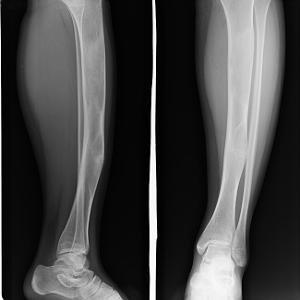

2、 多发型纤维结构不良 多发型病变较广泛,大约85%的病例会发生病理性骨折。症状发生早,可发生于全身多数骨骼,常累及一侧肢体,双侧肢体同时侵犯时可产生各种畸形。对于侵犯股骨的病人,可因多次病理性骨折产生髋内翻、肢体短缩等畸形。病情重者可出现典型的“牧羊人手杖”畸形。若病变发生在胫骨,可出现膝内翻、膝内翻、胫骨前凸、小腿过长等畸形。若病变发生在颅骨可出现额头突出,眼球突出并向外下方移位,即特殊的“狮面”面容。

单发型病变部位在髓腔内,长管状骨的干骺端或骨干中心位或偏心位。骨皮质变薄形成缺损,呈模糊的髓腔内放射透明区,常形容为磨砂玻璃状。多发型纤维结构不良常累及数骨,同侧的髂骨、股骨、胫骨、腓骨常被累及。四肢长骨病变常累及骨的全部,髓腔宽窄不均,其增宽处骨皮质变薄并扩张。部分高度膨胀,其中有囊性改变,常表现为病理性骨折。X线表现为溶骨范围界限不清,骨皮质缺损和临近软组织肿块通常提示恶变。